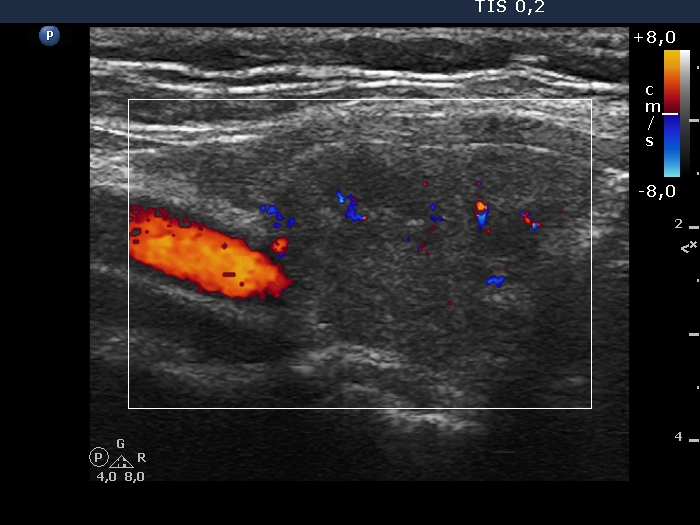

Examination in 2018 (second row of images):

Clinical data. The patient came to a routine follow-up. She had no complaints.

Palpation: unchanged.

Laboratory test: TSH 0.36 mIU/L on daily 125 microgram levothyroxine.

Ultrasonography. Except for the lesion which was previosuly cytologically investigated, the pattern remained unchanged. The lesion in question became cystic and was composed of two chambers. In the tissue part separating the two chambers, hyperechoic granules have appeared. These were mostly related to ventral cystic areas, therefore, they should be regarded as back wall figures.

We recommended that she takes the replacement therapy at the same dose and has a TSH scan after half a year and an ultrasound scan after two years.